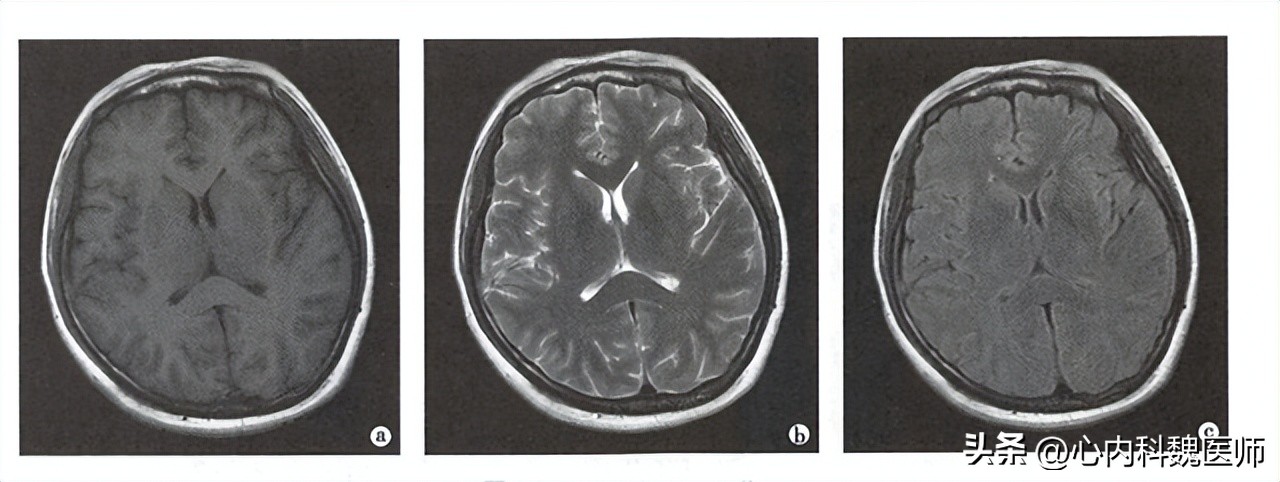

最后,结束射频这个力量,氢质子运动方向恢复的时间,经过计算机分析得到的黑白灰三个不同程度的显影,就是磁共振结果我们看到的图像,我们可以根据颜色的深浅,来判断疾病的发展程度。

1、颅脑损伤的运用最广:

颅脑里面包含的结构有血管组织,肌肉组织,和骨组织,所以运用磁共振进行扫描可以更加的全面。

其次磁共振可以对血液的特殊显影,迅速在脑部扫描后很快显影效果,如:脑出血、脑梗死等,对位置判断和出血、梗死范围都可以迅速定位。